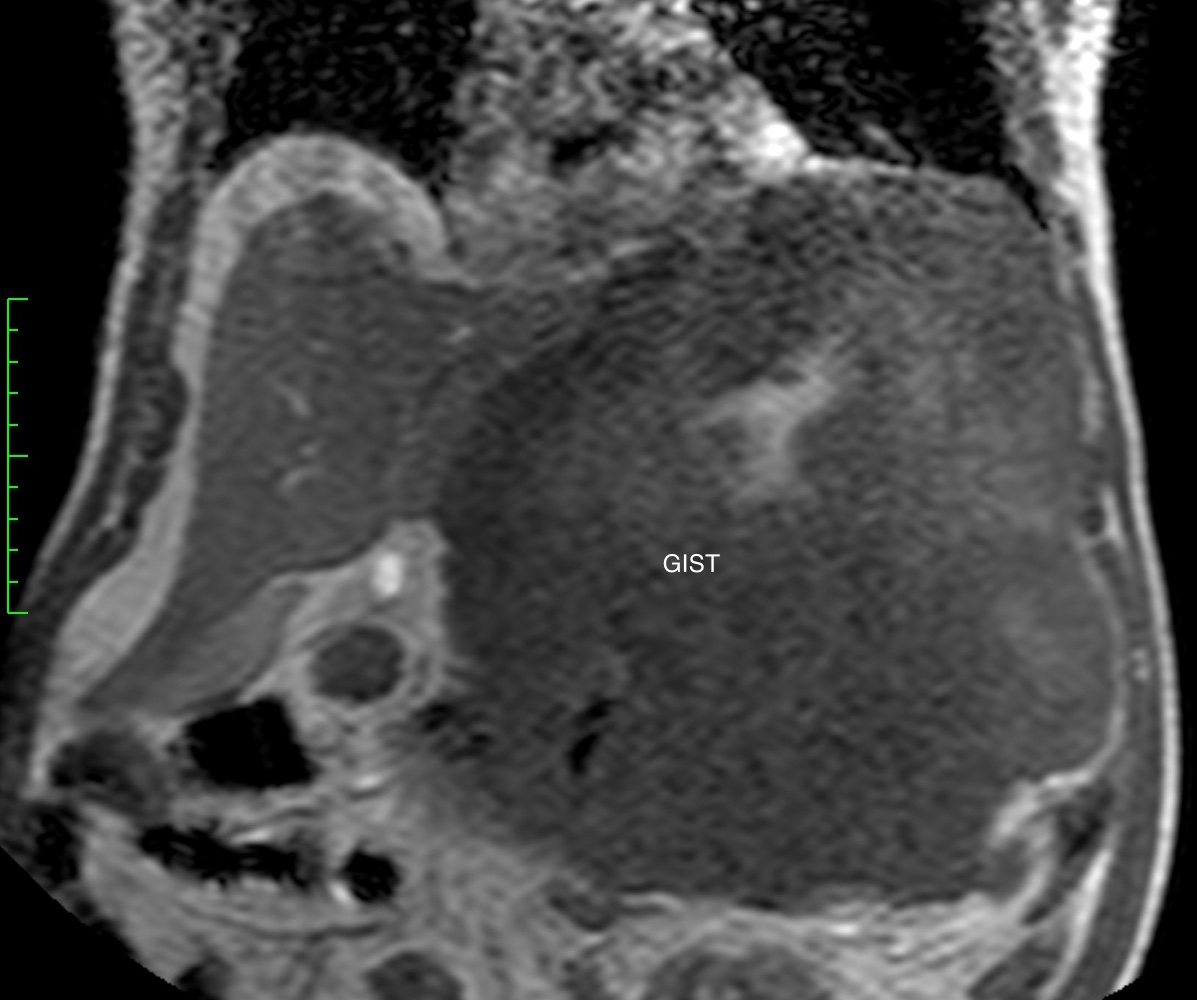

Гастроинтестинальная стромальная опухоль гигантских размеров, исходящая из большой кривизны желудка